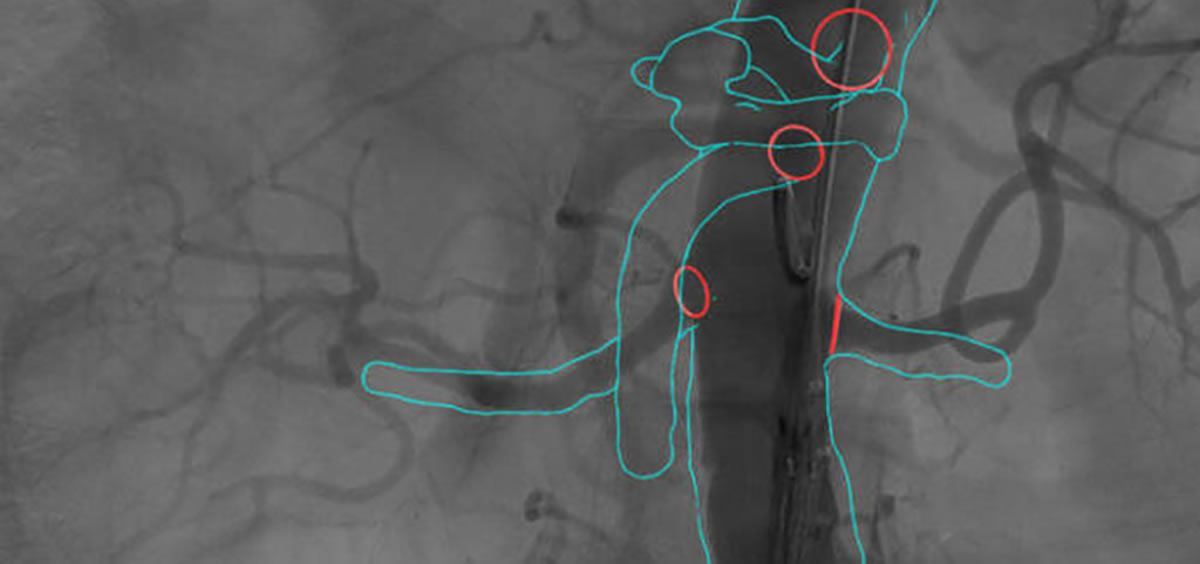

Se trata de Cydar EV, de Cydar Medical. La visión por ordenador patentada superpone automáticamente el mapa en la imagen de rayos X en vivo con mayor precisión y solidez.

Cuando las guías y los instrumentos deforman los vasos sanguíneos, se utilizan imágenes en tiempo real para actualizar el mapa para que coincida con la nueva anatomía deformada. El resultado es un mapa 3D preciso y receptivo en la pantalla durante todo el procedimiento.

Durante la cirugía endovascular, las guías rígidas suelen enderezar, acortar y desplazar los vasos sanguíneos. El cirujano utiliza agarraderas colocadas en los cables de las guías virtuales para ajustar la forma del mapa 3D para que coincida con la anatomía en tiempo real (transformación no rígida).

Una vez ajustado, el sistema recuerda ese ajuste en 3D incluso cuando el equipo de rayos X cambia de posición. Alternar entre el mapa preoperatorio y el mapa ajustado ayuda al equipo clínico a visualizar cómo ha cambiado la anatomía y posicionar los dispositivos con precisión. Esto reduce la duración del procedimiento entre 30 y 60 minutos en intervenciones endovasculares y la exposición a la radiación para los profesionales y los pacientes se reduce en un 50%, incluso en la REVA estándar.

La visión por ordenador patentada superpone automáticamente el mapa en la imagen de rayos X en vivo con mayor precisión y solidez